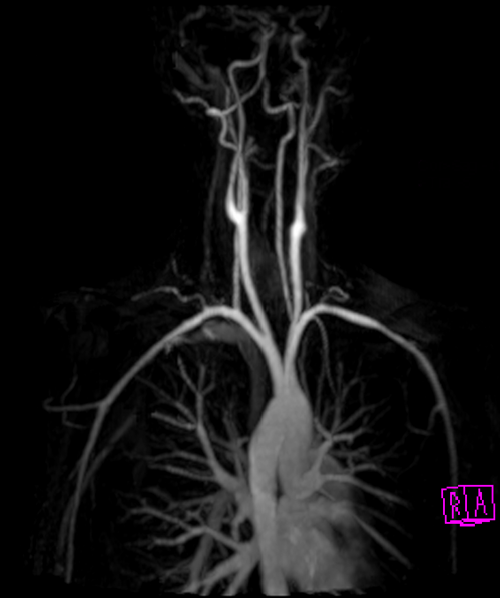

mri subclavian arm down mip 1 - MRI